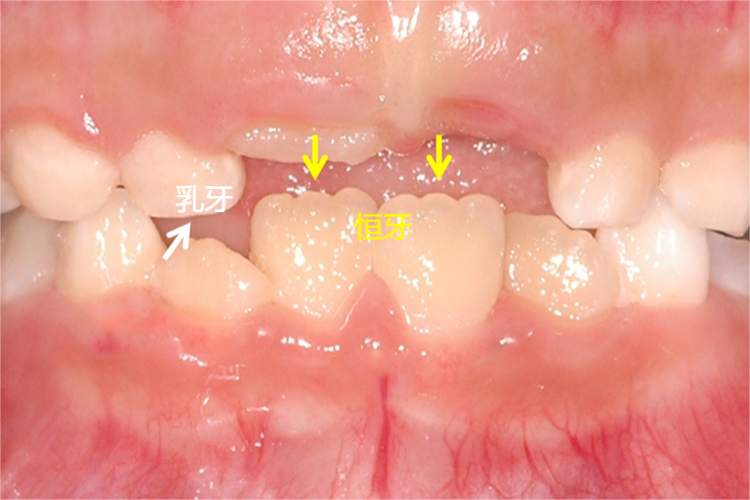

从外观上看,乳牙萌出早又易磨耗,故切、牙尖磨耗明显,乳牙色白或青白,牙冠高度短,近远中径相对较大,并具有牙冠近颈1/3处凸出明显、颈部收缩等特点,以同名的恒牙相比,乳牙比恒牙小。

从外观上看,恒牙新萌出不久,磨耗不明显,新萌出的恒切牙尚可见明显的切嵴结节,恒牙微黄,更有光泽。